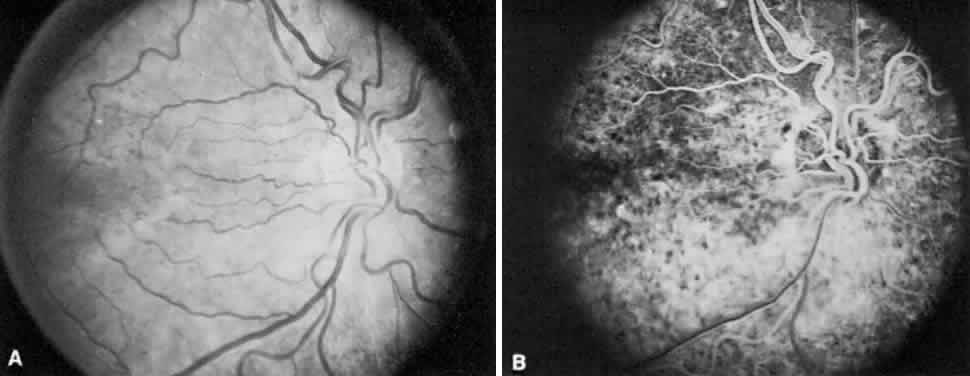

Fluorescein angiography usually demonstrates early hypofluorescence of a pit, and 50% progress to hyperfluorescence as the study continues (Fig. 9). Visual fields are abnormal in about 60% of eyes with pits; arcuate scotomas are the most commonly encountered defect.56

Fig. 9. A. Fluorescein angiogram in the laminar venous filling phase of an eye with an inferotemporal optic pit. The pit is hypofluorescent at this time. B. Ten minutes after the injection, the pit is hyperfluorescent.